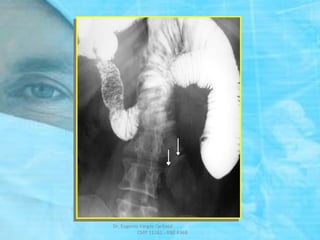

DEFINICION: PENETRACION DE UN

SEGMENTO INTESTINAL EN OTRO

ADYACENTE

TAC: INVAGINACION – INTUSUSCEPCION

SIGNO DE “SALCHICHA”

SIGNO DEL “TIRO AL BLANCO”

RARA VEZ SE ENCUENTRA EN

ADULTOS PERO CUANDO SE

PRESENTA LA CAUSA ES UN

“POLIPO” ó ALGUNA LESION

INTRALUMINAL

PORCENTAJE DE

CASOS DE

INTUSUSCEPCION:

ADULTOS: 5 %

NIÑOS: 95 %